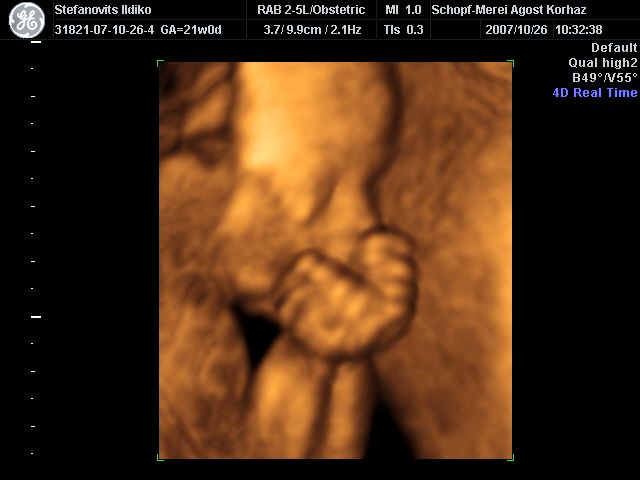

4D Ultrahang - 21+1 (07/10/26, Bp.)

4D - 5